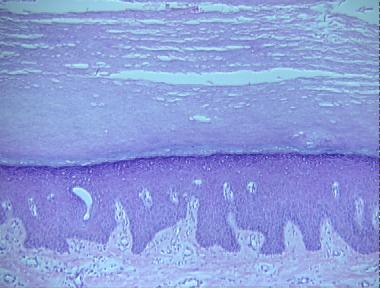

keratosis palmaris et plantaris

Histologic Features